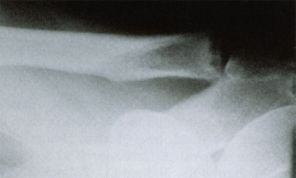

Schultereckgelenkarthrose (ACG-Arthrose)

Schmerzhafter Knorpelverschleiss des Schultereckgelenkes.

Bei konservativ nicht beherrschbaren Symptomen kann eine arthroskopische oder offene Entfernung des äusseren Schlüsselbeinknochens in Betracht gezogen werden (sog. ARAC-OP).

Bei nicht schmerzhaften Arthrosen, die aber durch Knochenneubildung eine Einengung der darunter verlaufenden Sehnen verursachen kann ggf eine reine Glättung durch Abfräsen von überstehendem Knochen erfolgen (sog. Co-Planing)